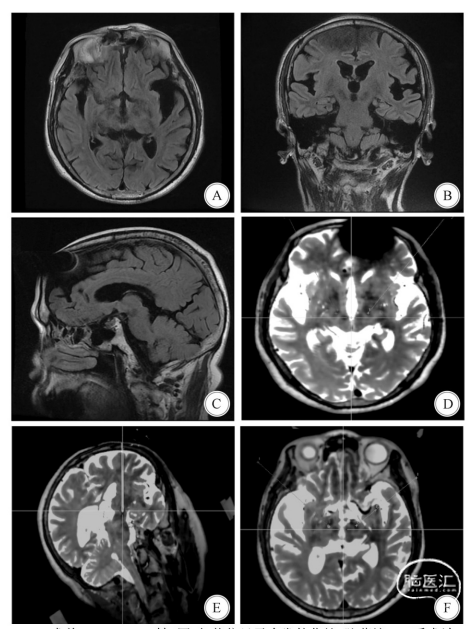

A—C:术前MR,FLAIR轴、冠、矢状位显示多发软化灶,脑萎缩;D:手术计划,靶点左(x:-14.5,Y:-3.5,z:-4.0),右(x:13.5,Y:-3.0,z:3.8);E:术后融合靶点,显示电极的针道路径;F:术后融合显示左侧偏差0.5mm,右侧偏差0.7mm

图1 病例1患者的影像资料、手术计划和融合后电极位置